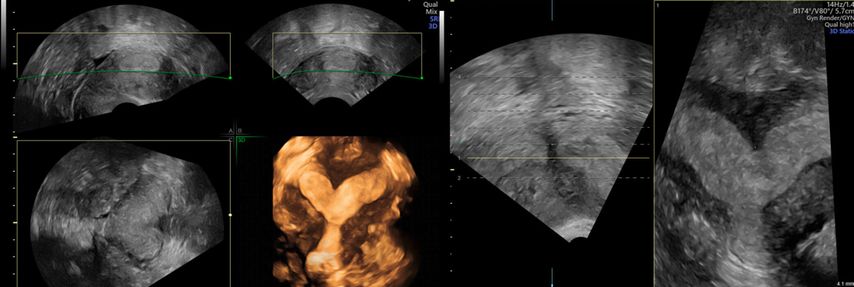

In unklaren Fällen, in denen die äussere Uteruskontur in der MPR nicht eindeutig zu sehen ist und so die Unterscheidung zwischen einem Uterus (sub-)septus und einem Uterus bicornis schwierig ist, hilft TUI bei der Differenzialdiagnose (Abb. 5 und 6).

Abb. 5: «Tomographic ultrasound imaging» (TUI). In mehreren parallelen Ebenen kann die äussere Uteruskontur analysiert werden (konvex vs. konkav)

Abb. 6: Uterus bicornis. Ist die äussere Uteruskontur in der MPR nicht eindeutig zu erkennen, hilft TUI (rechts)